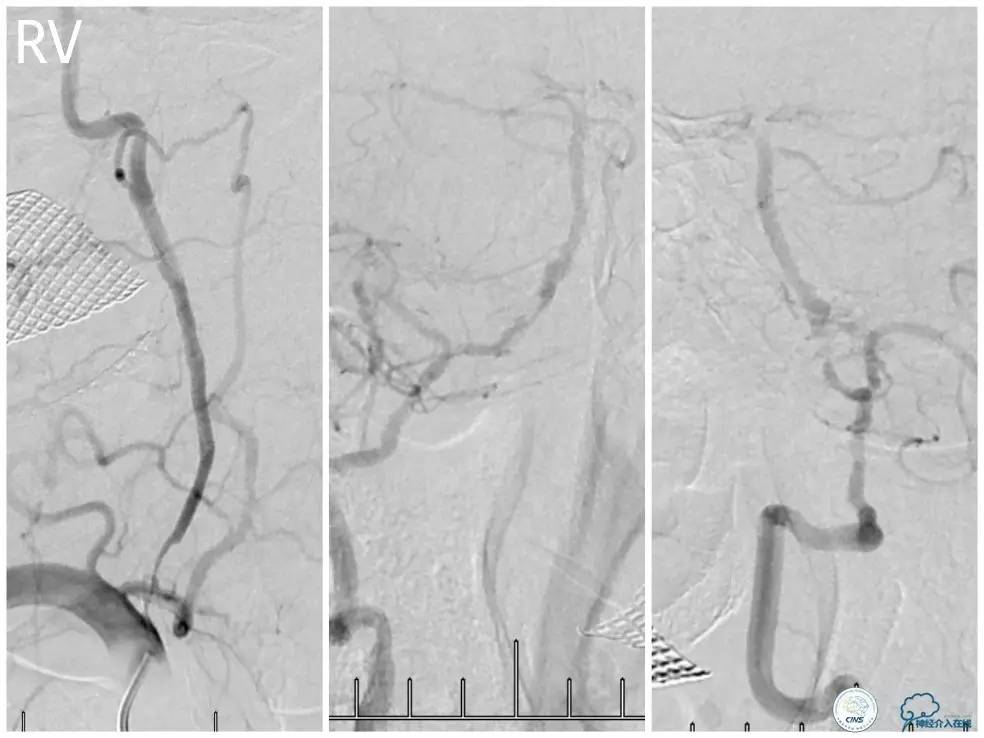

术前DSA:右椎动脉V1段长段重度狭窄,V4-基底动脉交界区显影浅淡,狭窄程度重,但具体程度显示欠佳(图7)。左椎动脉V1段闭塞,左椎动脉V2远段经侧支代偿显影,V3段以远未见显影(图8)。前循环造影未见明显前循环向后循环代偿(图9)。

图7

图8

图9

1. 患者右椎动脉优势,右椎动脉V1段长段重度狭窄、V4段-基底动脉重度狭窄(或者闭塞)。左椎动脉V1段闭塞,经侧支代偿的左椎动脉V3段以远未见显影亦考虑闭塞,拟处理右椎动脉。

2. 右椎动脉V1段狭窄程度重,病变长度长,但病变血管较为平直,估计先处理近端病变后导引导管越过支架难度不大,故决定先处理近端病变再处理远端病变。

3. 右椎动脉V4段-基底动脉长段狭窄,CT提示局部钙化明显,预计发生术中扩张困难的机率高,拟采用球囊预扩张,再放置自膨支架。